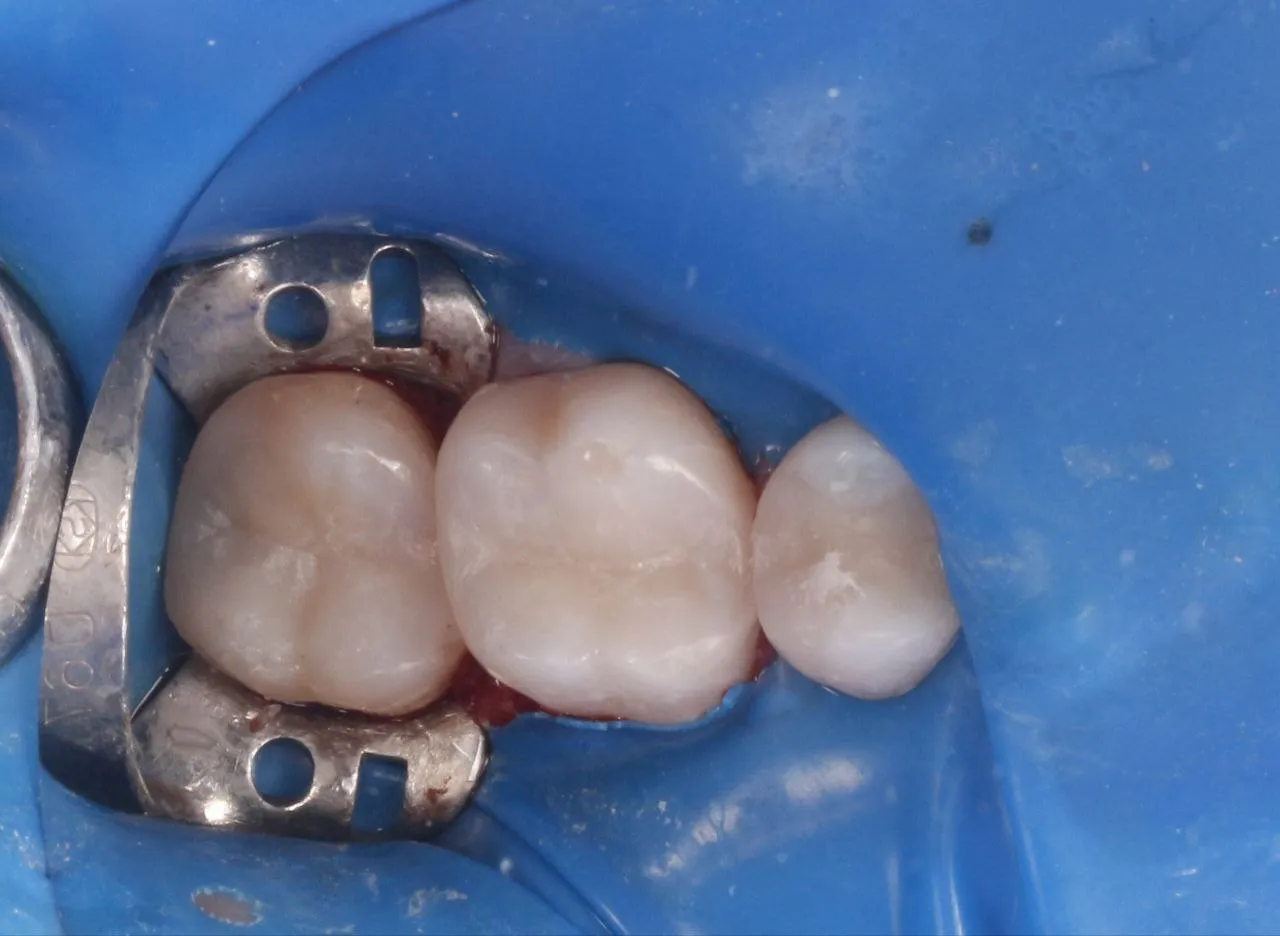

Лікування вторинного карієсу в зубах 47 та 45